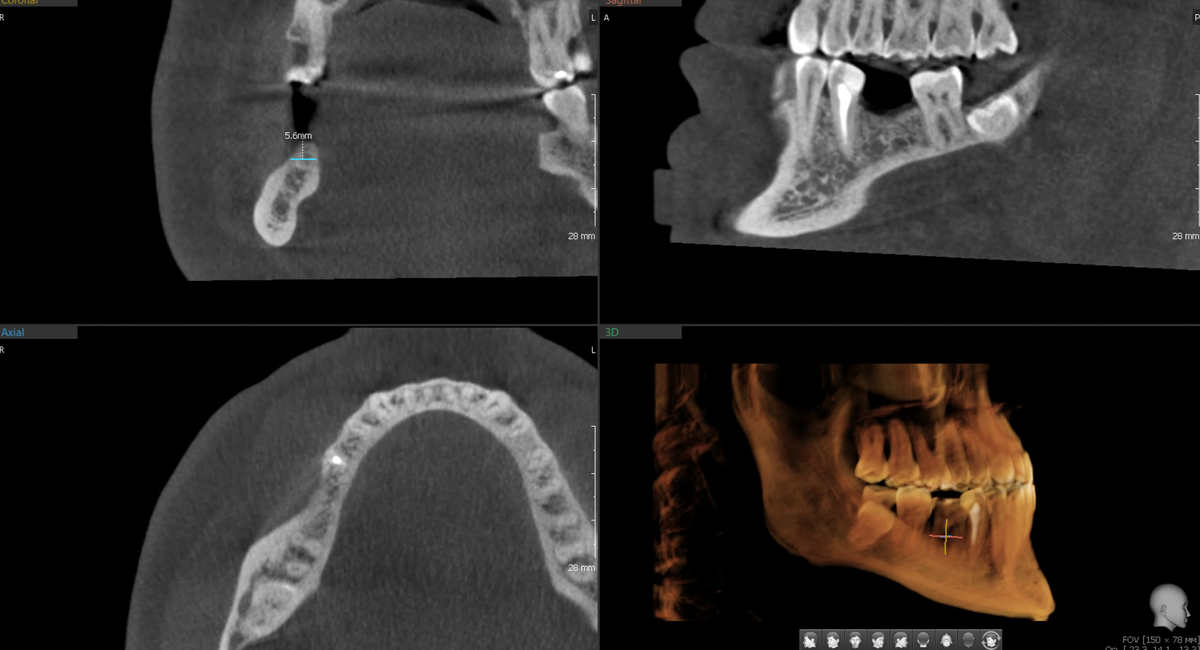

Цифровое планирование - математика против интуиции

Техник смоделировал будущую коронку в цифре. Не абстрактную, а конкретно под этого пациента - чтобы идеально встала в прикус, чтобы контакты с соседними зубами были правильные, чтобы жевательная нагрузка распределялась физиологично.

Хирург загрузил эту коронку в программу планирования, где уже были данные КТ:

-2

И цифровой слепок:

Имплантолог примерил имплантат под цифровую коронку и вот что выяснилось - кости хватает, но впритык. Если ставить имплантат диаметром, максимум, 4.1 мм - всё хорошо помещается в кости. При 4.3 мм - уже нет, упрёмся в кортикальные пластинки.

Казалось бы, 0.2 мм - ерунда. Но в имплантологии это критично.